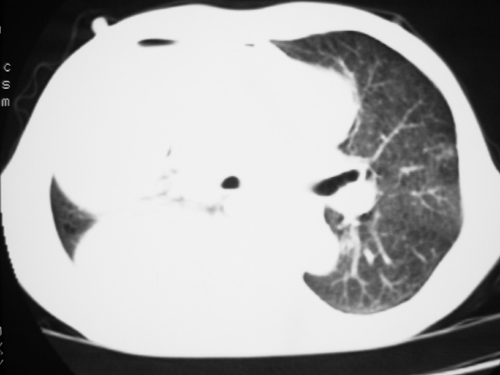

以下是引用yangyudong333在2008-4-29 5:46:00的发言:[br]1左上叶结节呈分叶状,边缘毛刺,考虑肺癌并纵隔淋巴结转移可能性大,结核待排,[br] [br]2右侧多发包裹性胸腔积液